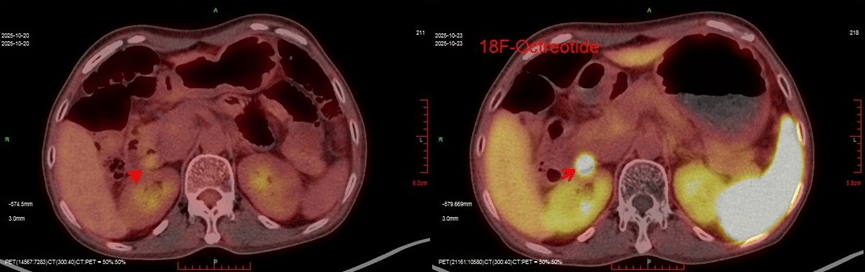

明确方向后,王凌云主任迅速联系医院核医学科李丹副主任,为吴女士安排了目前最具特异性的检测手段—18F-奥曲肽PET/CT。

影像检查结果显示:在十二指肠球降交界处,一个病灶异常“高亮浓集”,提示此处存在一个生长抑素受体高表达的神经内分泌瘤。进一步的超声胃镜确认了该占位性病变。与此同时,一个治疗中的细节也印证了判断:吴女士对质子泵抑制剂反应极佳,服药后症状很快缓解。最终,血清胃泌素水平检测(585pg/ml,远超正常值)一锤定音,吴女士确诊为胃泌素瘤。

图说 / 影像检查精准锁定病灶位置